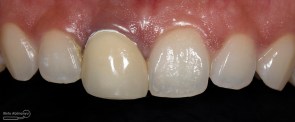

Kondisi awal saat pasien datang

dan saya lebih terkejut ketika melihat foto ronsennya

Setelah saya perhatikan memang crown tersebut terlihat lebih opaque dibanding gigi2 di sebelahnya…